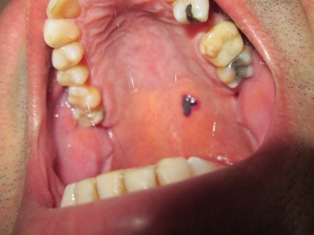

ho 55 anni e da circa 2 anni con una frequenza più o meno trimestrale, nel palato molle compaiono improvvisamente delle vescichette che fanno pensare alla rottura di un capillare.

Con la stessa velocità con cui si formano altrettanto rapidamente scompaione nel giro di massimo un giorno.

Provocano un leggero dolore simile ad una irritazione.

vescichetta.JPG [32.32 KiB]